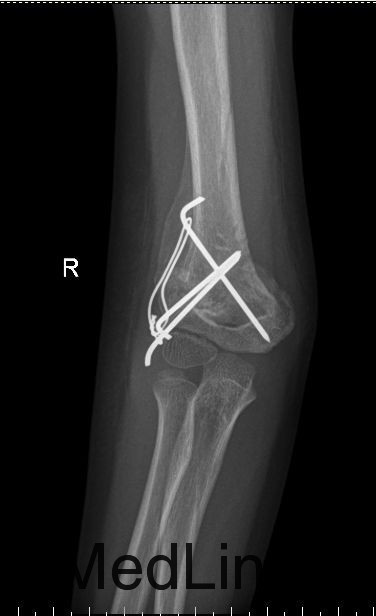

诊断:右侧肱骨髁上骨折 治疗:全麻下行“右侧肱骨髁上骨折切复内固定术